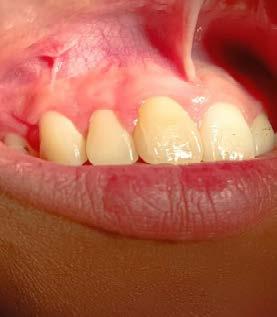

Figura 4. Imagen representativa de una férula flexible en la superficie labial del órgano dental afectado y en los dientes adyacentes. Tomada por el esp. Isidro Valdez Ramírez.

Figura 5. Imagen representativa del resultado del tratamiento. Tomada por el esp. Isidro Valdez Ramírez.

Un método de tratamiento para dientes traumatizados es la ferulización dental (Figura 4), que permite la curación del tejido periodontal y al mismo tiempo protege el diente de lesiones adicionales. La fijación flexible o semirrígida es suficiente para la curación pulpar y periodontal en la mayoría de las TDI, y la fijación rígida solo se recomienda para las fracturas de la raíz cervical. Si la anquilosis no supone un riesgo significativo, se recomienda entre 1 y 2 semanas durante el periodo de fijación. Sin embargo, si las lesiones traumáticas incluyen destrucción del hueso, pueden ser necesarias de 1 a 2 semanas adicionales, y en caso de fracturas de raíz, pueden ser necesarios hasta 4 meses de inmovilización.15

En comparación con la intrusión y la avulsión, la luxación extrusiva se caracteriza por un menor daño al periodonto. El aspecto clínico es un diente alargado y con excesiva movilidad. Radiográficamente se puede observar un aumento en el espacio del ligamento periodontal apical. El tratamiento recomendado es reposición del diente lo antes posible, uso de férulas, tratamiento de endodoncia y control clínico y radiográfico (Ver Tabla 3).16